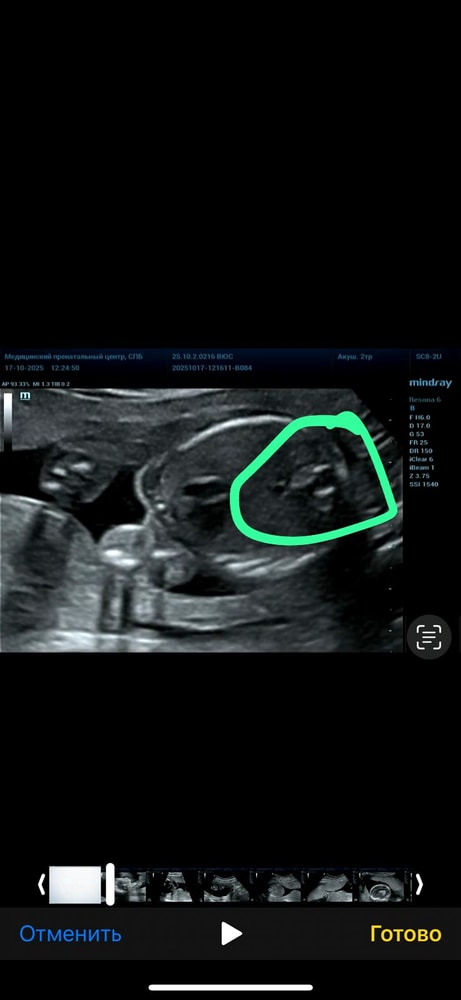

Анализы, скринингиВот и сделала я второй скрининг, получила видео с узи, когда смотрела узи (доктор не разу не выключал экран) то по видео поняла, что мальчик 🤣 нам дали конвертик с полом, на котором уже было все напечатано (не от руки) и запечатан с двух сторон, переживаю была ли ошибка в конверте. Я вижу мальчика 🤣 а на конверте девочка. У меня есть два сына и я уже боюсь узи 🤣

срок беременности 19 недель и 5 дней

Просто мне кажется что там выше рядом еще третье что-то 🤣